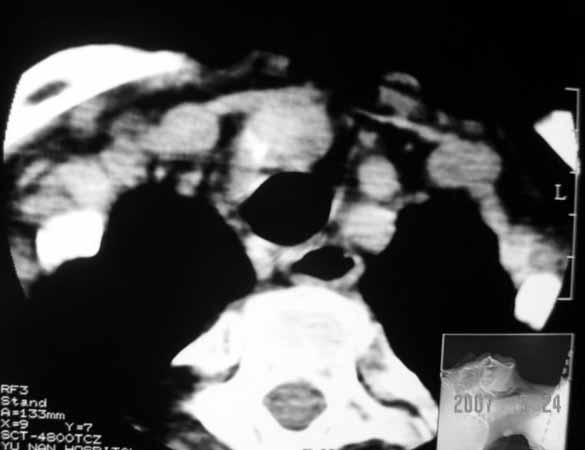

以下是引用jw-830在2007-5-24 15:33:00的发言:[br]右侧甲状腺增大,内可见低密度,病灶与周围软组织界线欠清晰,建议增强扫描除外甲状腺癌

以下是引用adams在2007-5-24 17:15:00的发言:[br]支持“ 右侧甲状腺增大,内可见低密度,病灶与周围软组织界线欠清晰,建议增强扫描除外甲状腺癌”。 [br] [br] [br][br] [br] [br]

以下是引用苯小孩在2007-5-24 15:26:00的发言:[br]左侧甲状腺腺癌或瘤,建议穿刺或核素进一步检查.